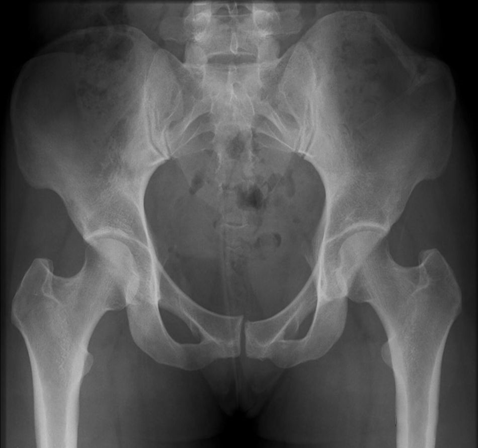

(3)Pipkin 骨折

髋关节后脱位往往合并股骨头骨折(5-15%)。最早(1957 年)由 Pipkin 描述并分类,因而被命名为 Pipkin 骨折,常见于屈膝屈髋位汽车仪表盘损伤。